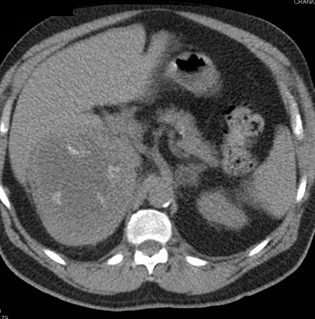

The most likely dx in this case of a newly detected adrenal mass is?

lymphoma

primary adrenal carcinoma

old adrenal hematoma

metastatic melanoma